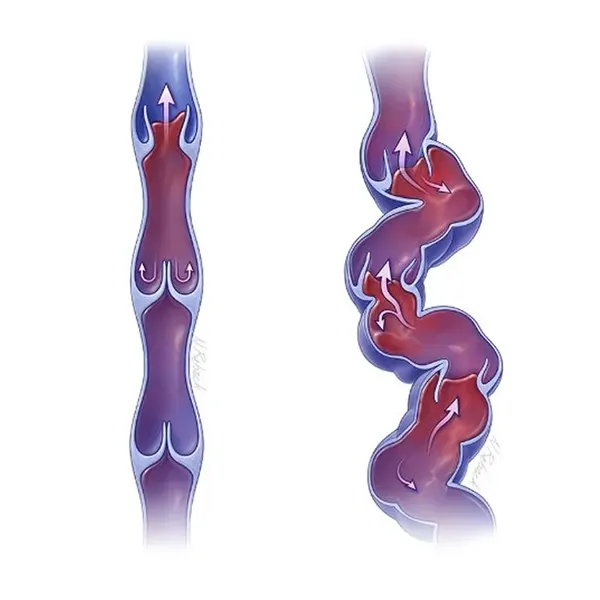

As veias varicosas são um tipo de varizes, que apresentam veias dilatadas, tortuosas e insuficientes, normalmente localizadas nas pernas, que se tornaram anormalmente inchadas e geralmente apresentam um diâmetro maior que 3 milímetros.

A cor destas veias varia de azul a roxo escuro e são muitas vezes salientes, aparecendo sob a pele como cordões nodosos.

O sangue nas pernas deve fluir para cima em direção ao coração. Para prevenir o fluxo sanguíneo para baixo, as veias têm válvulas unidirecionais.

Quando estas válvulas não funcionam corretamente, o sangue pode acumular-se nas veias, causando a dilatação que conhecemos como veias varicosas.